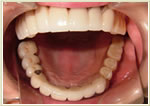

◆崩壊咬合治療症例

症例1 32歳 男性 画像拡大

治療前 治療後